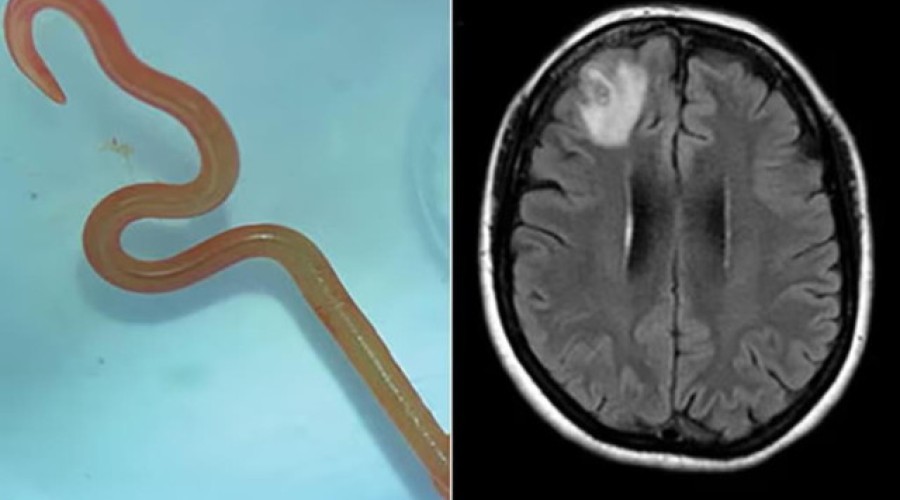

O neurocirurgião, Dr. Hari Priya Bandi, retirou um verme parasita de 8 centímetros de comprimento do cérebro de uma paciente, o que a levou a procurar Senanayake e outros colegas do hospital para obter conselhos sobre o que fazer a seguir.

Segundo o jornal The Guardian, a paciente já tinha sido internada em janeiro de 2021 com queixas de febre, dores abdominais e diarreia incessantes, tosse seca e suores noturnos. Em 2022, a estes sintomas juntaram-se sinais de depressão e perda de memória, o que levou ao seu encaminhamento para o hospital de Canberra. Feita uma ressonância magnética que revelava algumas anomalias, a mulher foi operada ao cérebro.

Ophidascaris robertsi é um verme geralmente encontrada em cobras pítons e a paciente do hospital de Canberra marca o primeiro caso mundial do parasita encontrado em humanos.